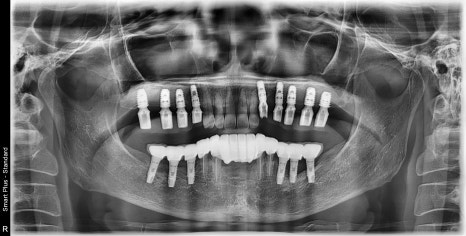

다수의 임플란트 식립 시 내비게이션 사용 / 광범위한 골이식 증례

양쪽 어금니가 발치된 지 오래된 상태셨고

위턱뼈의 뼈가 임플란트를 식립하기에는

너무 얇은 상태였습니다.

아래 앞니들은 치주염으로 인한 발치가 필요한 상황이며

위 앞니는 무너진 교합 때문에

앞으로 튀어나고 벌어져 있었습니다.

뼈가 너무 얇지만 광범위한 뼈이식 동시에

임플란트까지 식립하는 것을 목표로 하고

수술시간 단축을 위해 3D 내비게이션 가이드를 제작했습니다.

다행히 골이식과 동시에 임플란트를 수술 성공하였습니다.

수술은 결과적으로 성공적이었고

붓기는 조금 있으셨지만

환자분께서 잘 도와주신 덕분에

잘 마무리할 수 있었습니다.